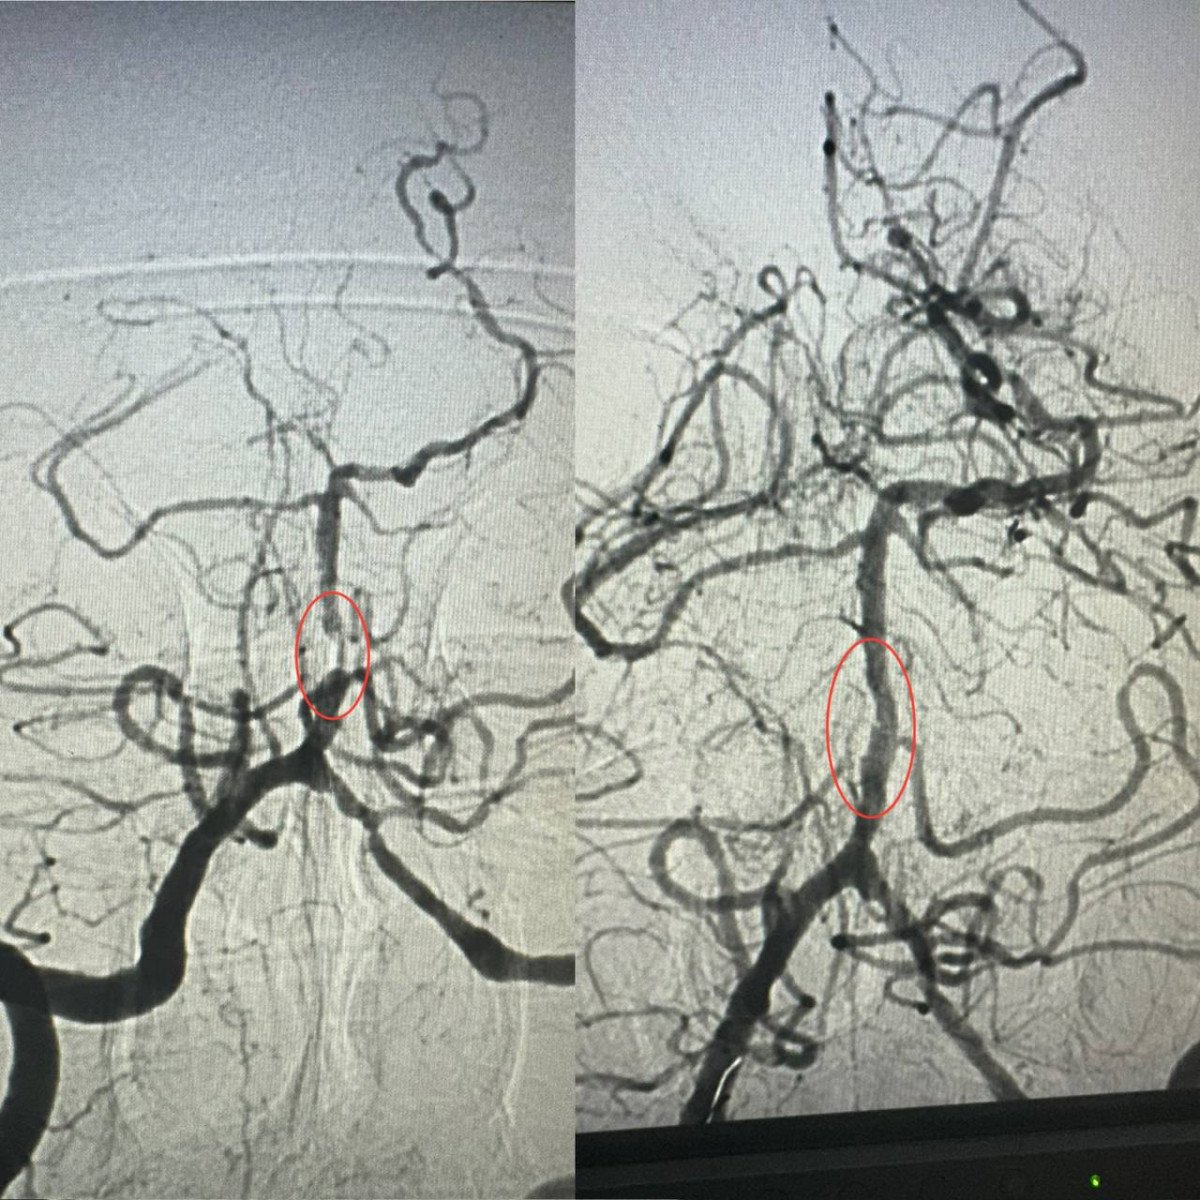

Як розповів завідувач рентгенендоваскулярного блока лікарні Олександр Скрипка, це був один з найскладніших випадків - ураження стовбурової частини мозку. Базилярна артерія була майже повністю закрита атеросклеротичною бляшкою. Такі інсульти належать до найбільш небезпечних, а за відсутності термінової допомоги навіть шанси на виживання мінімальні.

Фахівці прийняли рішення оперувати та провести ангіопластику артерії. Кластерна лікарня №10 має досвід такої методики лікування в кардіології при атеросклерозі коронарних судин, але застосування її для мозкових судин - це інноваційна технологія в масштабах України.

Операція тривала близько 60 хвилин. Звужену артерію розширили за допомогою спеціального балона, а потім застосували балон з лікарським покриттям.